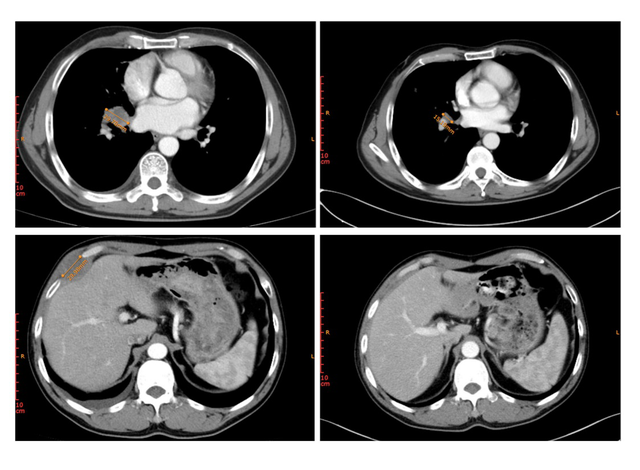

患者3为晚期肺鳞癌,化疗进展后接受MRG003治疗,右肺门处病灶同样在MRG003治疗后得到显著缩小,靶病灶直径总和缩小54.1%。

患者2为右肺腺癌患者,治疗前右门病变与右胸壁转移性肿瘤大小将近30mm,MRG003治疗后右门病变从29.78mm缩小至15.19mm,而右侧胸壁转移瘤已经几乎看不见。